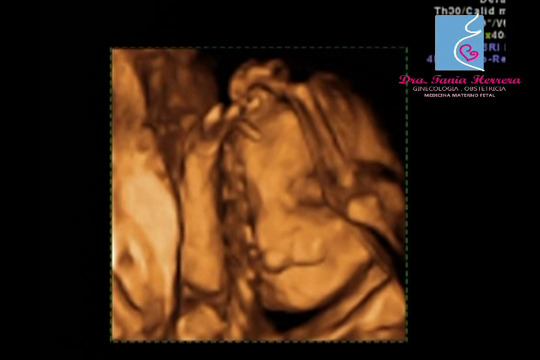

Una de las patologías que se pueden observar es el Labio Hendido en un simple corte Bidimensional, siempre y cuando los brazos no tapen la cara del bebé.Importante descartar Paladar hendido y nunca confundirse con Ausencia de Premaxila, ya que orienta hacia otros diagnósticos, principalmente anomalías cerebrales.